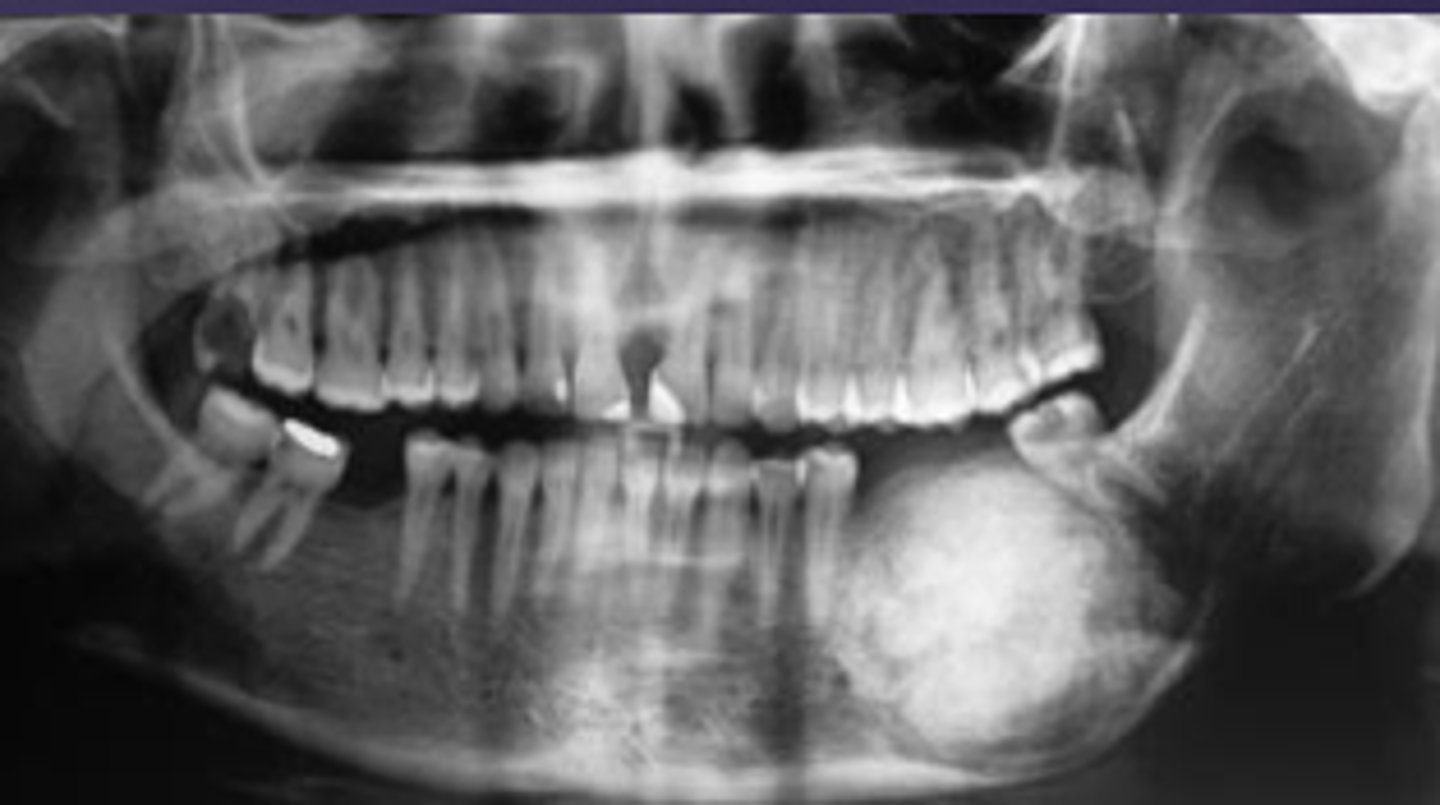

How would you describe the lesion?

- Well-defined corticated multilocular radiolucency in the right ramus

- Mandibular body causing root resorption

- Expansion and thinning of anterior wall of ramus, coronoid process, inferior border of mandible

- Displacement of the inferior alveolar canal

What category would this lesion be part of?

Benign

What would be a differential diagnosis for this lesion?

- Ameloblastoma

- OKC